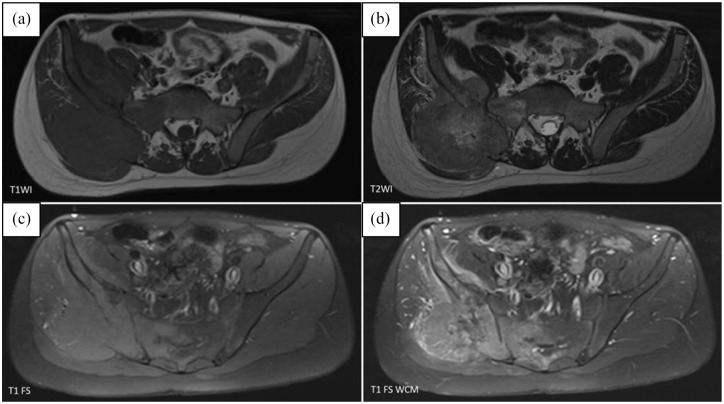

Case presentation: We present a case of 16-year-old patient with Ewing sarcoma diagnosed with neoplastic fever.